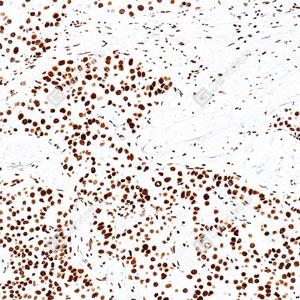

| IHC检测Histone H4蛋白(货号 GB151842). 样品: 人肝癌, 4%多聚甲醛 (货号G1101) 固定12-24小时. 抗原修复: 抗原修复仪(货号 ARI-4),柠檬酸抗原修复液(干粉, pH 6.0) (G1201), 高压锅均匀喷气计时2分钟. —抗: 1: 1000稀释, 4℃ 孵育过夜. 二抗: S-vision免疫组化多聚二抗(山羊抗小鼠), 即用型(货号G1301), 室温孵育20分钟. |

| IHC检测Histone H4蛋白(货号 GB151842). 样品: 人肺癌, 4%多聚甲醛 (货号G1101) 固定12-24小时. 抗原修复: 抗原修复仪(货号 ARI-4),柠檬酸抗原修复液(干粉, pH 6.0) (G1201), 高压锅均匀喷气计时2分钟. —抗: 1: 1000稀释, 4℃ 孵育过夜. 二抗: S-vision免疫组化多聚二抗(山羊抗小鼠), 即用型(货号G1301), 室温孵育20分钟. |